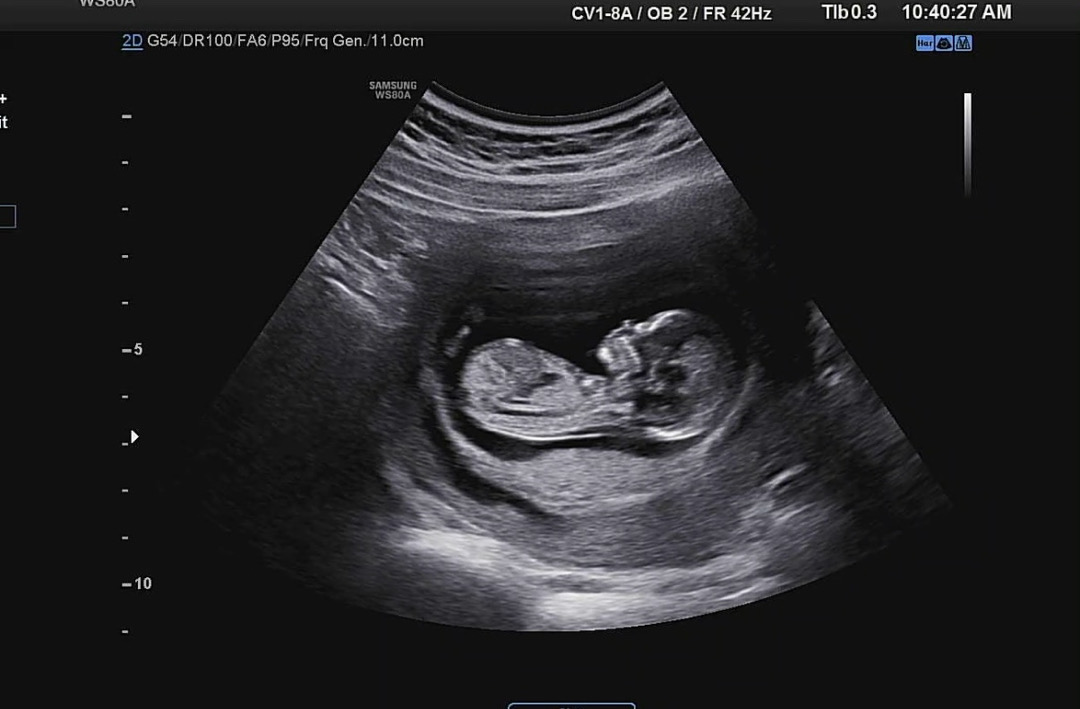

15주 저도 살짝 올려봐요,,👼🏻💗

아무리봐도 초보엄마는 각도법을 모르겠어요.. 딸인지 아들인지 시간되실때 한번 봐주셔요..🩵

하체와 생식기부분이 안보이는 각도의 사진인것같아요~